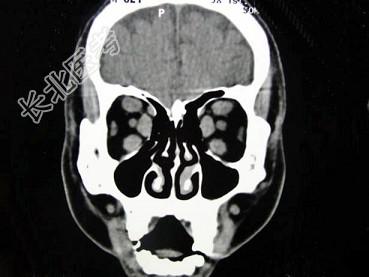

- 单项选择题女,50岁, 消瘦、多饮多食,脖子粗大, 双侧眼球突出1年余,CT检查如图所示, 应考虑为 ( )

A、眼型格氏病

B、甲状腺眼病

C、炎性假瘤

D、横纹肌肉瘤

E、眶部结核